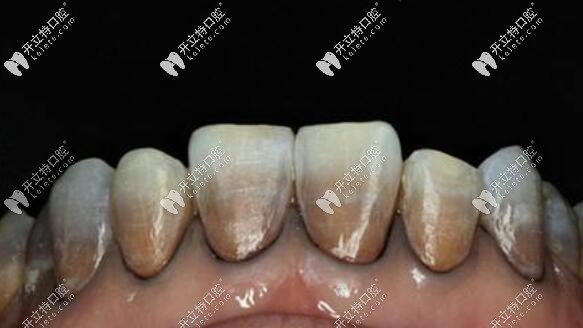

重度四環(huán)素牙照片↓↓↓

瑞典全瓷冠對(duì)圖片中的重度四環(huán)素牙有不錯(cuò)效果